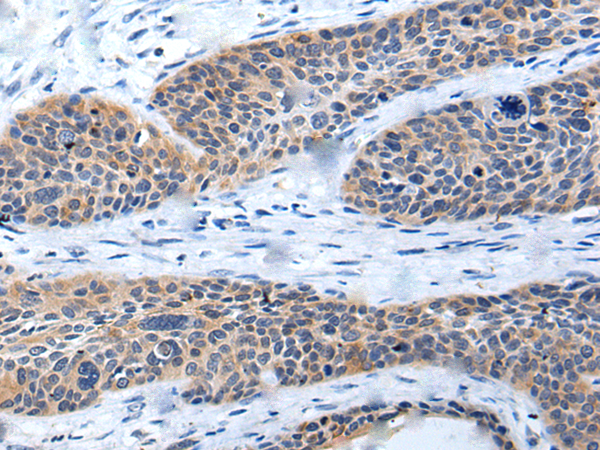

IHC positive control: |

Human ovarian cancer and human cervical cancer |

IHC Recommend dilution: |

25-100 |